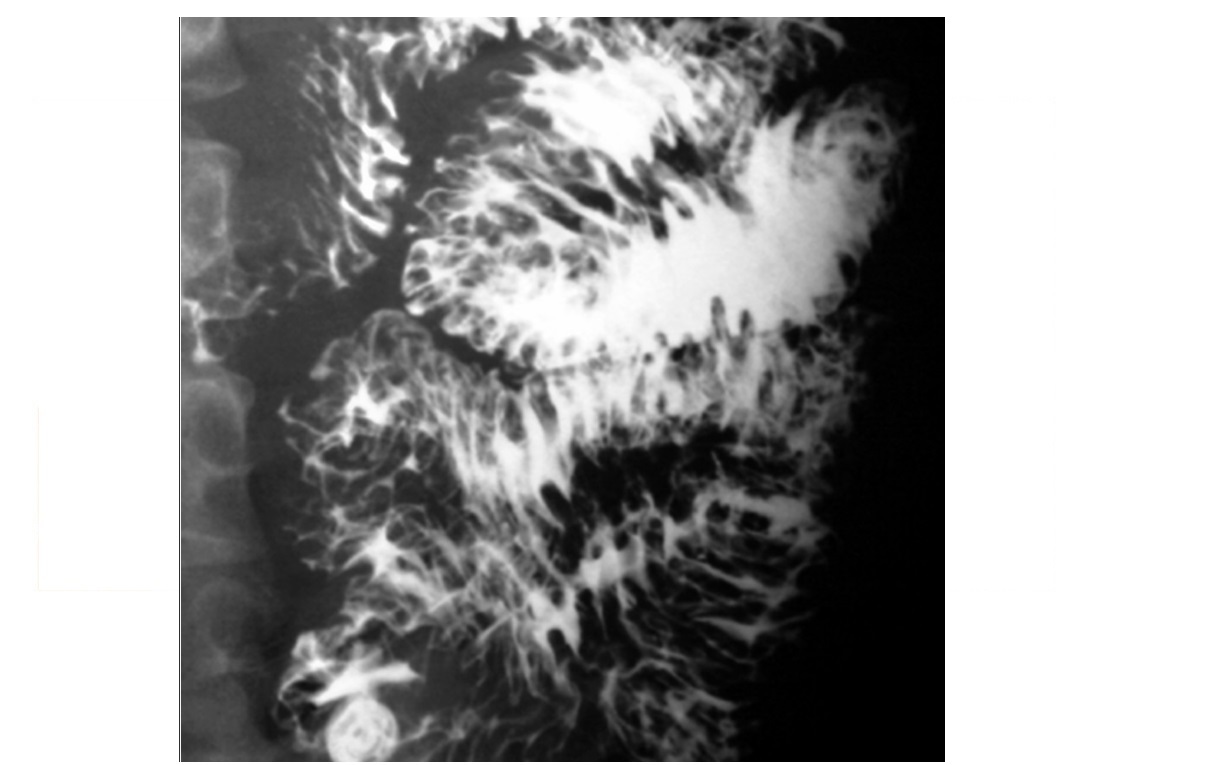

Candidiasis

irregular, longitudinal plaques with intervening normal mucosa

Typically upper 1/3 oesophagus